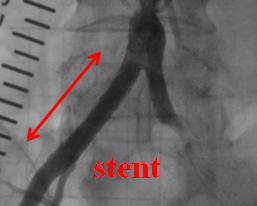

PTA(経皮的血管形成術)

足の血管が狭くなると、しばらく歩くと足が痺れたり、痛みが出現するが、休憩をすると元に戻るという症状が出現します。腎臓の血管が狭くなると血圧上昇や腎機能低下をきたす原因にもなります。経皮的血管形成術とは心臓以外の血管(例えば手足の血管や腎臓の血管など)が動脈硬化により血管内腔が狭くなった所を風船やステント(金属のコイル)を用いて、広げる治療です。足に関しては治療が成功すると痺れたりすることなく歩行が可能となり、腎臓に関しては血圧や腎機能の改善を認めるようになります。